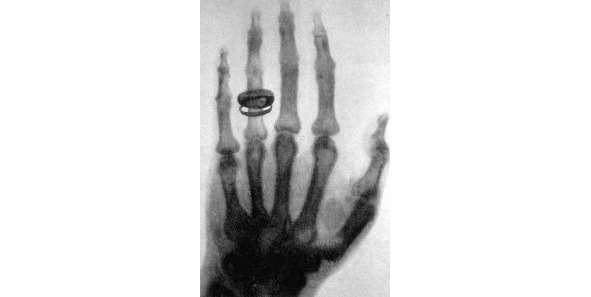

Главное открытие в своей жизни Конрад Рентген сделал 8 ноября 1895 года. Работая в своей лаборатории, он обратил внимание на то, что после включения тока в катодной трубке, почему-то начинает светиться покрытый слоем платиноцианистого бария бумажный экран. Причем происходило это вопреки «здравому смыслу», поскольку трубка была полностью закрыта плотным черным картоном, а значит, свет не мог проходить через него. Он выключил ток – свечение прекратилось, включил – экран снова засветился! И тогда он сделал вывод, что в трубке возникают икс-лучи, которые способны проходить через плотный материал, и заставляют флуоресцировать особые вещества. Причем в зависимости от вида материала и его толщины, преграда пропускала больше или меньше лучей. Как следствие, стало возможным анализировать структуру различных объектов. Установка, разработанная Рентгеном, выполняла совершенно новую функцию – неразрушающий анализ структуры непрозрачного объекта.

Рисунок 2. Первый рентгеновский снимок – рука Альберта фон Кёлликера, 21.01.1896 года